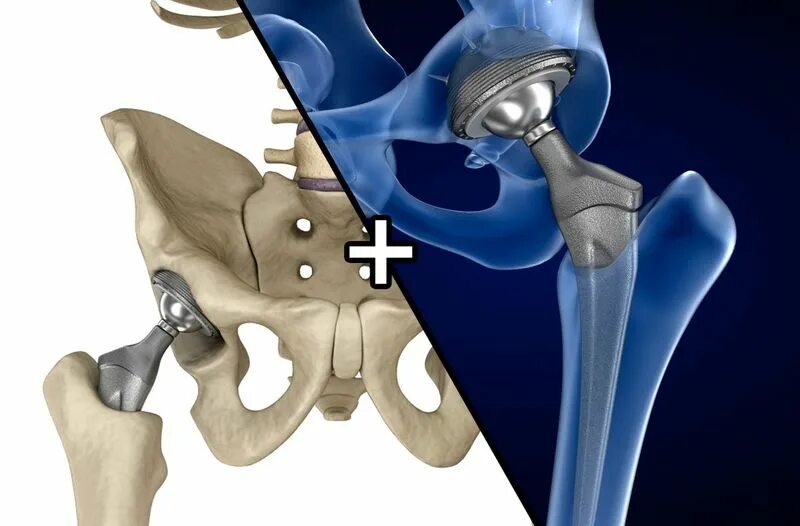

Эндопротез тазобедренного сустава москве